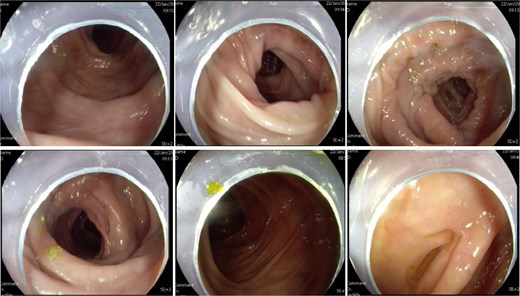

Colonic transit time assessment was performed using radiopaque markers. At 24 h post-ingestion, 19 markers were retained within the colon, with complete clearance observed at 48 and 72 h, confirming normal colonic motility (Fig. 2). Defecography demonstrated a Grade III RC, characterized by a maximal depth of 76 mm during straining and persistent barium retention post-evacuation, consistent with obstructed defecation syndrome (ODS) (Fig. 3).